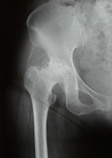

本邦では主として骨盤の臼蓋形成不全(発育不全)並びに先天性股関節脱臼などは軟骨が体重の負荷で磨り減り、骨頭と臼蓋がすりあうことで痛みや炎症を招きます。

レントゲンで変形がみられても、痛みの程度が軽い場合は薬による治療・理学運動療法などで対処しています。 ですが、歩くことが困難な場合や痛みが激しい病状の際には、人工関節手術などの手術療法が必要になってきます。